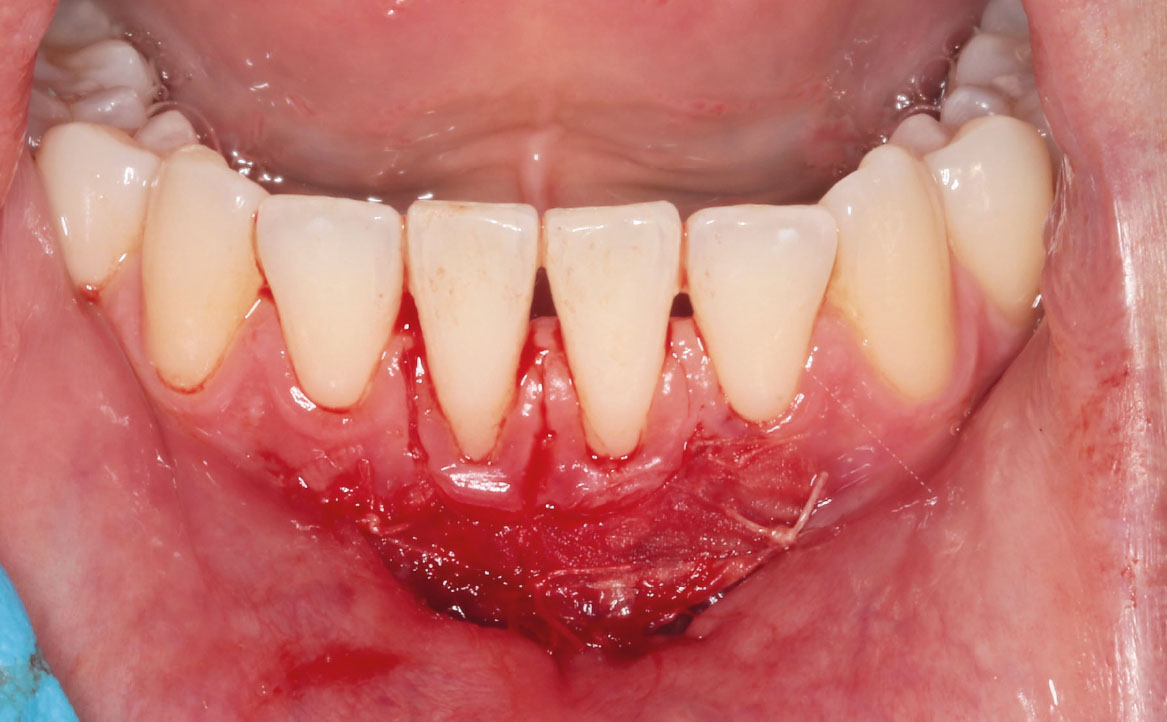

Previa anestesia loco-regionale plessica con lidocaina, è stata eseguita un’incisione parallela rispetto alla cresta alveolare e scollamento della mucosa mediante un laser neodymium yttrium aluminum garnet laser (Nd:YAG, 1064nm, 3.75W, 75Hz) (fig. 4-5).

Successivamente, i margini epiteliali e il tessuto sottomucoso sono stati fissati con punti di sutura singoli usando fili riassorbibili 5/0 Vicryl (fig. 6). Sul fondo del difetto chirurgico è stato applicato un gel di acido ialuronico reticolato, xHyA (composizione: 1,6% acido ialuronico reticolato, 0,2% acido ialuronico nativo) (fig. 7). L’acido ialuronico (o ialuronano, HA) è un glicosamminoglicano formato da un’unità disaccaridica (acido glucuronico e N-acetilglucosammina) che si ripete fino a 50.000 volte. Questa molecola è normalmente presente nel nostro organismo dal momento che rappresenta uno dei principali componenti della matrice extracellulare (5). L’HA è una sostanza igroscopica e viscoelastica (6), che svolge un’azione batteriostatica (7), antinfiammatoria (8,9) e antiedematosa (10). Inoltre, lo ialuronano sembrerebbe rivestire un importante ruolo nella rigenerazione tissutale, prendendo parte e accelerando le fasi del processo di guarigione delle ferite (11,12).